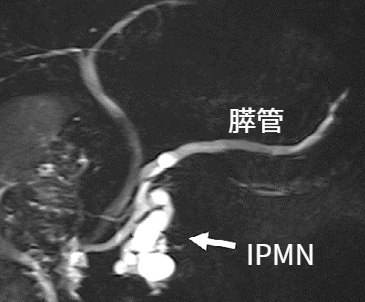

膵管内乳頭粘液性腫瘍(IPMN)

膵がんの前癌病変

粘液を分泌する良性の膵のう胞性疾患で、多くの場合無症状です。

IPMNの診断、がん化率

IPMNの診断は、超音波検査(エコー)やCT・MRI検査で行います。

がん化率は、大きさや形、種類によって様々ですが、1年間に1-10%、10年間で10-70%と考えられています。